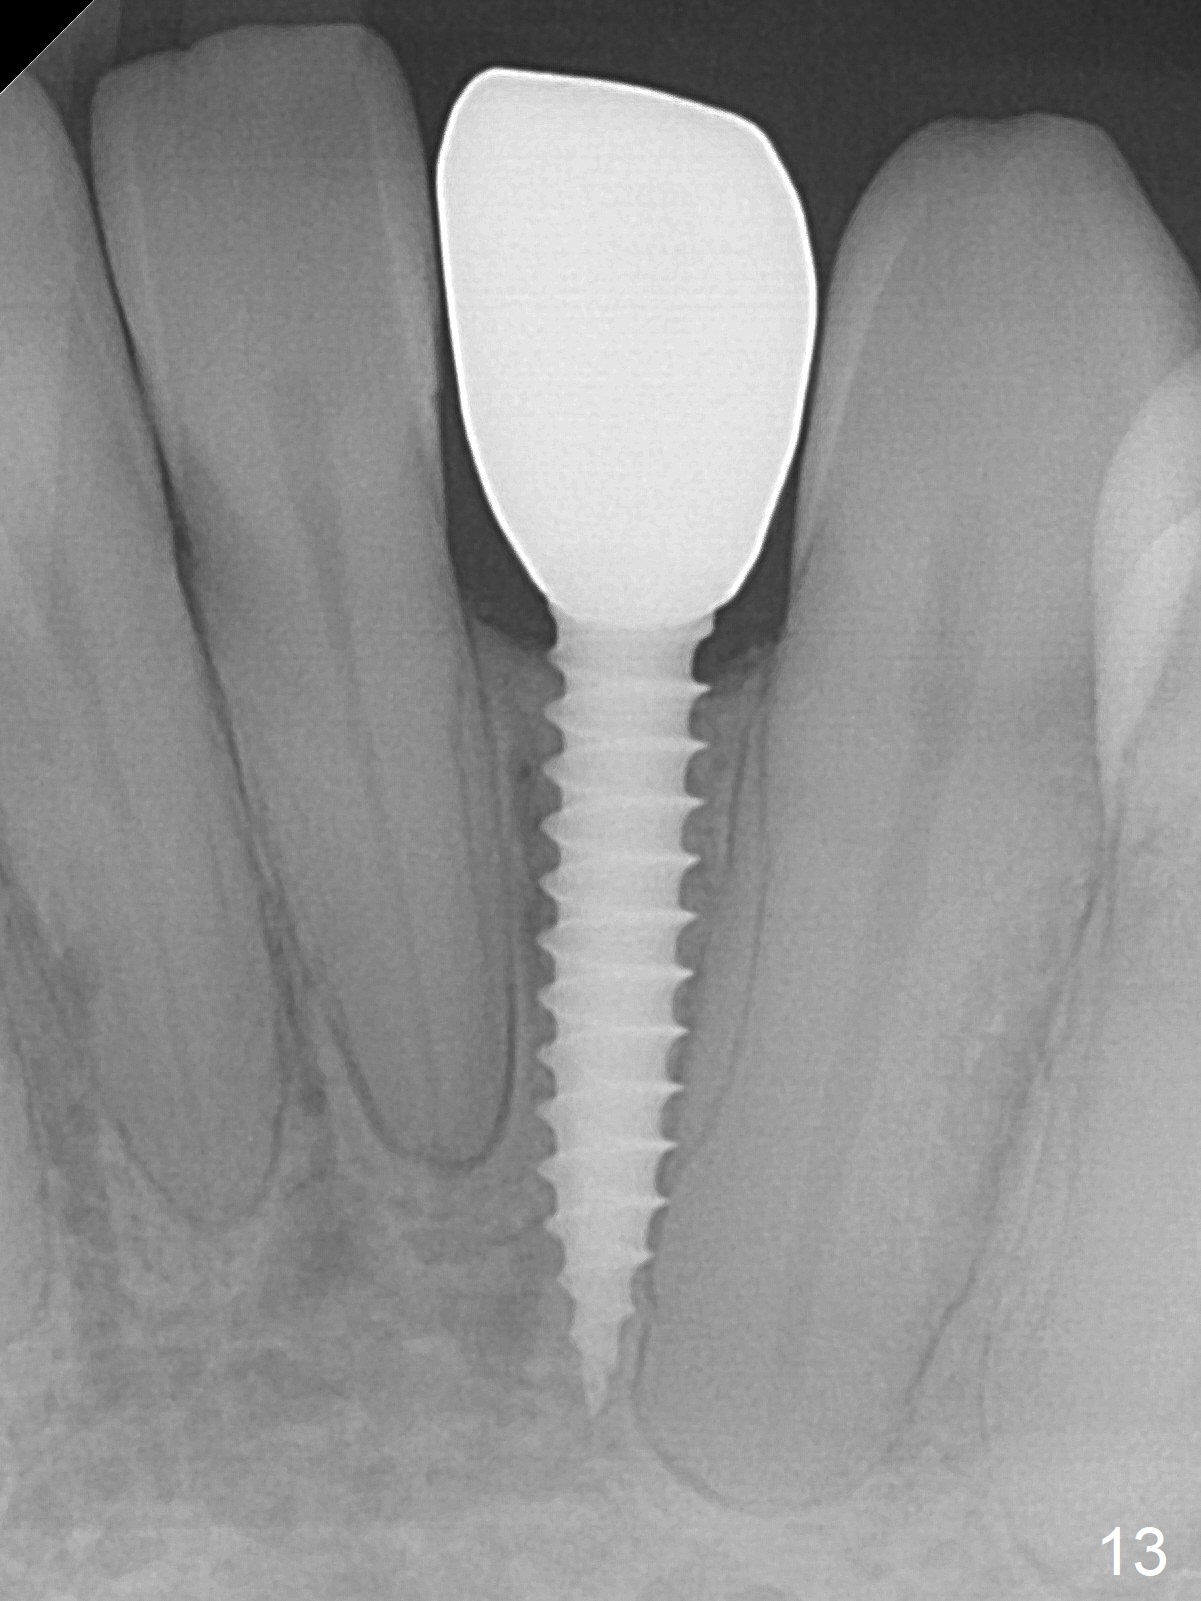

Within the first several days postop, the patient reports mild tenderness from one of the neighboring teeth. Otherwise she is doing fine. Again due to finance, she does not return for restoration for more than 1 year. PA taken 10 months postop shows that there is no abnormality (Fig.7). In fact bone resorption occurs gradually over 2 years 2 months postop, manifested as the 1st thread supracrestal (Fig.8 <). When the 1-piece implant is reprepped for impression 2 years 2 months postop, the micro threads are found apical to the prep margin (Fig.9). The nervous patient has had occasional tooth sensitivity 5 years postop. A narrower implant is more suitable for this case (2.0 or 2.5 mm).

Fig.10: A2 shade guide. The patient requests A1 for the incisal edge and body and A2.5 for the cervical region. Fig.11 is taken 22 months post 2nd cementation (4 years postop). The implant crown remains normal 1 year 10 months post 2nd cementation (4 years 10 months postop, Fig.12,13).